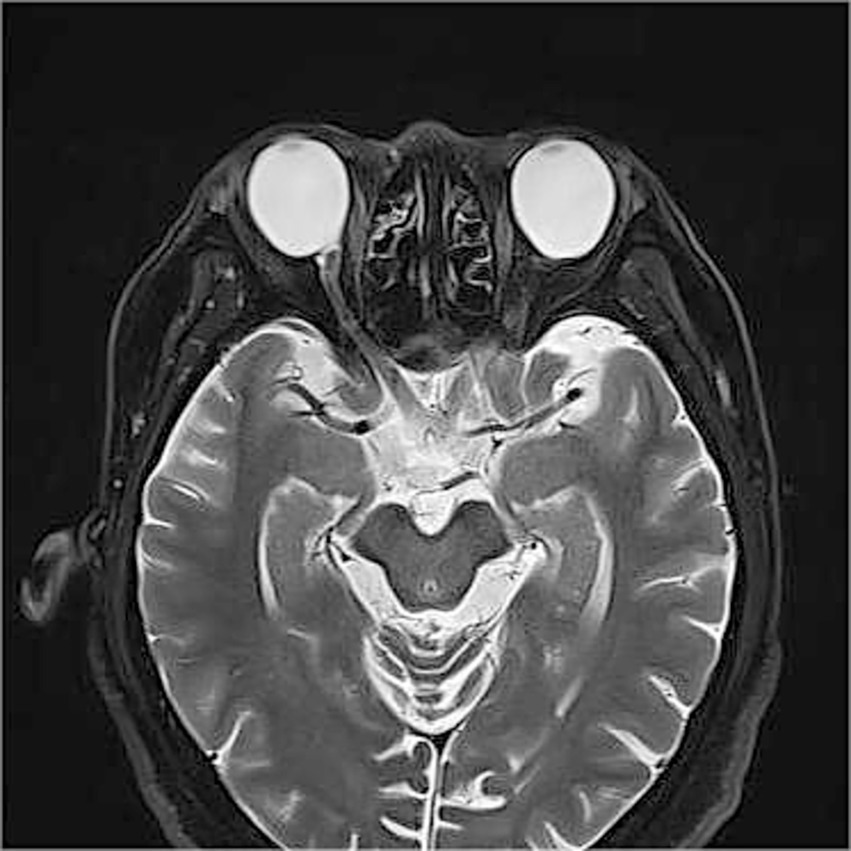

Given the extreme rarity of duplication of the optic disc, multimodal imaging, including MRI, FFA, ICGA, and OCT, was performed for further characterization. Orbital MRI revealed marked axial elongation with posterior staphyloma in both eyes; however, only a single optic nerve was identified (Figure 2). On FFA (HRA Spectralis; Heidelberg Engineering, Heidelberg, Germany), retinal vessels were clearly visible in the optic disc at 24 s, while the pit showed no obvious vessels (Figure 3A). At 3 min 35 s, the optic disc exhibited hyperfluorescence, in contrast to the non-hyperfluorescent pit (Figure 3B). ICGA (HRA Spectralis, Heidelberg Engineering, Heidelberg, Germany) demonstrated that, at 16 s, the vessels around the pit filled synchronously with other choroidal vessels, a pattern consistent with perfusion by the short posterior ciliary arteries (SPCAs). At 20 s, the choroidal vessels were clearly visualized, followed by the initial filling of the retinal arteries (Figure 3C). At 3 min 35 s, ring-shaped staining was observed along the pit margin (Figure 3D). OCT (Spectralis OCT; Heidelberg Engineering, Heidelberg, Germany) revealed a localized, deep excavation within the area of posterior staphyloma and chorioretinal atrophy, characterized by an abrupt change in the scleral curvature. The pit measured 1,328 μm in width and 675 μm in depth (Figure 4A). Within the pit, the sclera appeared thin, the choroid was absent, and the retina demonstrated schisis at its base and margin. In contrast, the true optic disc, located in the peripapillary staphyloma of the same eye, was associated with a temporal scleral ridge and nasal retinoschisis; its excavation was shallower and flatter than that of the disc-like pit (Figure 4B). Based on these multimodal imaging findings, the disc-like lesion was definitively diagnosed as MMP. The patient subsequently underwent bilateral cataract surgery to address lens opacity. No intervention was performed for the fundus lesion. Postoperatively, the BCVA improved to 1.70 logMAR and remained stable along with the OCT findings, at the one-year follow-up.

Figure 2

Orbital magnetic resonance imaging (MRI) findings. Orbital MRI demonstrates axial elongation with posterior staphyloma in both eyes. Only a single optic nerve is identified posterior to each globe.